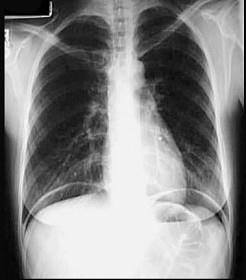

腹部受钝性暴力闭合性损伤,X线检查膈下有游离气体提示 ( )A、脾破裂B、膀胱损伤C、腹壁损伤D、胃肠道破裂E、肝破裂

问题 腹部受钝性暴力闭合性损伤,X线检查膈下有游离气体提示 ( )

选项 A、脾破裂 B、膀胱损伤 C、腹壁损伤 D、胃肠道破裂 E、肝破裂

答案 D